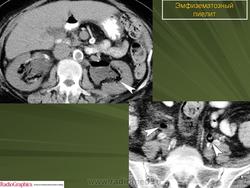

Эмфизематозный пиелонефрит

ID: 12239 Emphysematous pyelitis Dr Nasir Siddiqui - 2 Nov 2010 Gas within the transplanted right renal pelvis with mild hydronephrosis ...

ID: 20237 Emphysematous pyelitis Dr Zeyad Metwalli - 8 Nov 2012 Foci of air which conform to the renal calyces in this diabetic patient ...

ID: 17283 Emphysematous pyelonephritis Dr Maulik S Patel - 1 Apr 2012 Emphysematous pyelonephritis